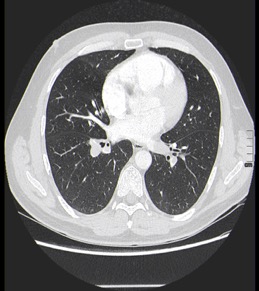

Nuestro paciente tiene síntomas respiratorios y un valor elevado de Dímero D. El Angio-TC nos permite hacer una valoración más detallada del estado de la anatomía vascular pulmonar así como del del corazón: También nos va a proporcionar una visión más en detalle del parénquima pulmonar.